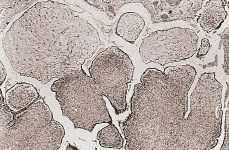

Realizamos estudios de inmunohistoquímica, para lo cual seleccionamos varias secciones de material embebido en parafina tanto del tumor como de otros tres casos de cistoadenofibroma de ovario, usados como control y comparación. Utilizamos el método de Streptoavidina-Biotina (Vectastain®), con pretratamiento proteolítico, usando los siguientes anticuerpos primarios: Anti-citoqueratina humana 8 (35ßH11, Dako Corp.), anti-citoqueratina de alto peso molecular (34ßE12, Dako Corp.), anti-citoqueratina humana 19 (K-19, Dako Corp.), anti-citoqueratina humana 18 (K-18, Dako Corp.) y anti-citoqueratina 5D3 (Menarini), todas ellas a una dilución de trabajo de 1:50. Los resultados obtenidos fueron idénticos tanto para el tumor paratubárico como para los tumores ováricos: fuerte positividad (3+), en la mayor parte de las células epiteliales para la citoqueratina 5D3 y la K-19 (Fig. 3), y débil positividad (1+) para las citoqueratinas K-18, 35ßH11 y 34ßE12. No observamos ningún tipo de diferencia de tinción entre los distintos tipos de células epiteliales de tapizamiento de las papilas, ni entre las papilas, ya fueran de estroma fibroso, edematoso o mixto.

Figura 3.Intensa positividad citoplasmática del epitelio superficial de tapizamiento de las papilas para la Citoqueratina 19 (Streptavidina-Biotina, x 400).